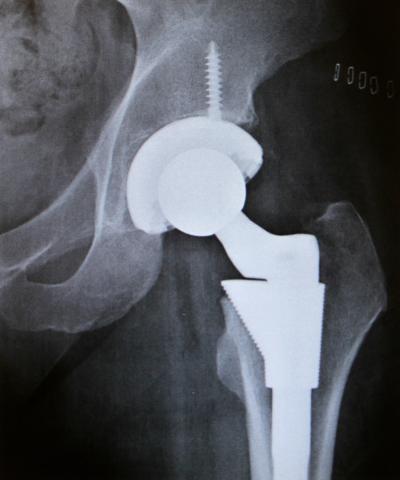

Imagine what Paula Spurlock must have been going through. Shortly after having a hip replaced in 2011, the trouble started. "I had horrible itching, really bad migraines and intense pain throughout my body," she said. "I couldn't take it. Every single thing in me itched."

More than a year after it was implanted, tests showed Paula was highly allergic to the metal in her new hip and to the surgical cement often used to hold joints in place. "That's the one thing that never occurred to any of us," she said. "No wonder I was miserable."

After having her metal hip removed and replaced with a ceramic model, Paula Spurlock's life is back to normal. "I haven't had any migraines or itching or any problems," she said. "It's been wonderful." But, she cautions, if you even think you have an allergy to metal, get it checked out before implant surgery. "It's really important that we get that out there," she said, "so others can can avoid all the things that I went through. It was a very long and miserable year and half."